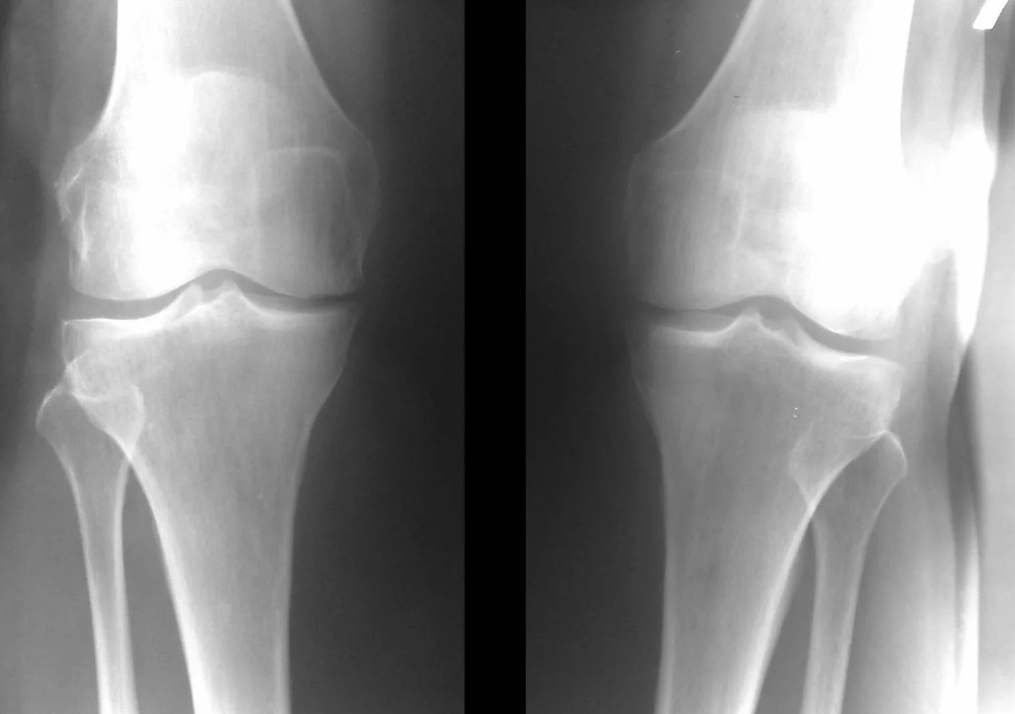

Instrumentele diagnose van artrose van het kniegewricht

In de overgrote meerderheid van de gevallen is een onderzoek en röntgenfoto van het kniegewricht in twee projecties (direct en lateraal) voldoende. Klinische gegevens en beelden helpen bij het bepalen van het stadium van de ziekte.

In de vroege stadia van de ziekte, met kleine veranderingen in het botweefsel, is röntgenonderzoek niet zo waardevol. In dit stadium kan gonartrose worden gediagnosticeerd door middel van artroscopie. De nauwkeurigheid van de methode is zeer hoog; alleen de invasieve aard en de prijs ervan kunnen dit tegenhouden.